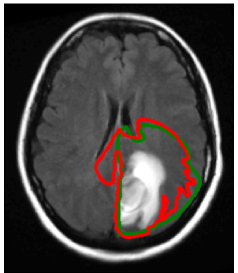

3.1 Target volume definition

Figure 4 shows the clinical target volume (dark green contour) and the boost volume (green contour) drawn manually by the physician, i.e. these contours were the basis for the treatment plan that was actually delivered to the patient. The prescribed dose to the boost volume was 60 Gy, the prescribed dose to the CTV was 46 Gy. The boost volume is defined based on a 2 cm isotropic extension of the contrast enhancing lesion. The CTV is defined via a 1.5 cm expansion of the T2-FLAIR abnormality. Both volumes were subsequently trimmed manually to account for anatomical boundaries (dura, ventricles, falx, and tentorium cerebelli). The dose distribution of the 3D conformal treatment plan delivered to the patient is shown in figure 6d.

Using the tumor growth model, the target volume can be defined as an isoline of the tumor cell density. This is illustrated here for the tumor cell density shown in figure 3a obtained for the parameter value Dw/Dg=100subscript𝐷𝑤subscript𝐷𝑔100D_{w}/D_{g}=100. The red and the orange contours in figure 4 show the CTV and the boost volume derived from the tumor growth model, respectively. In this example, the target defining isolines are chosen such that the total enclosed volume is equal to the manually delineated target. In the following two subsections, we discuss the differences between manual and model-derived target volumes in detail.

Refer to caption

Figure 4: Comparison of manually defined targets (light/dark green) and model derived targets (orange/red). In the clinical treatment plan, the light green volume was prescribed to 60 Gy, the dark green volume to 46 Gy. The yellow contour shows the abnormality on T2-FLAIR.

3.4 Difference in target volumes

In order to quantitatively compare the difference of manual and model-derived target volumes, we calculate the Dice coefficient, which is given by the volume where both structures overlap, divided by the average volume of the two structures. For the boost and CTV volumes in figure 4 the Dice coefficients are 0.78 and 0.77, respectively. Thus, three quarters of the manual target is also contained in the model-derived target, but a substantial portion of approximately one quarter is different.